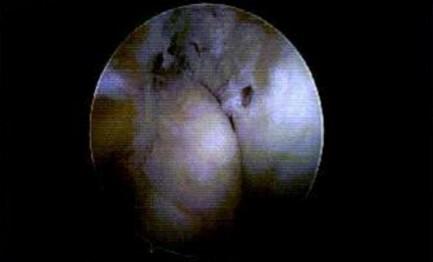

768 Use of Diagnostic Musculoskeletal Ultrasound in the Evaluation of Piriformis Syndrome: A Review for Rehabilitation Providers.

Manske RC, Wolfe C, Page P, Voight M, Bardowski B.